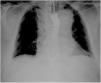

Fifty-seven-year-old male with a past medical history of high blood pressure and hiatal hernia admitted to the ER with clinical signs of syncope and chest pain. He is diagnosed with a Stanford type A aortic dissection and immediately referred to urgent surgery. After the intervention, the patient is admitted to the Intensive Care Unit. In order to guarantee enteral nutrition a nasogastric tube is inserted with difficulties when trying to move the tube forward. Its positioning is verified through the use of contrast and its malposition is eventually confirmed (Fig. 1). The thoracic coronary CT angiography shows a dissection-induced aortic hematoma causing an extrinsic esophageal compression with progressive tapering and dilatation prior to the obstruction (Fig. 2). Eventually, the patient requires endoscopic implantation to resolve the esophageal stenosis.